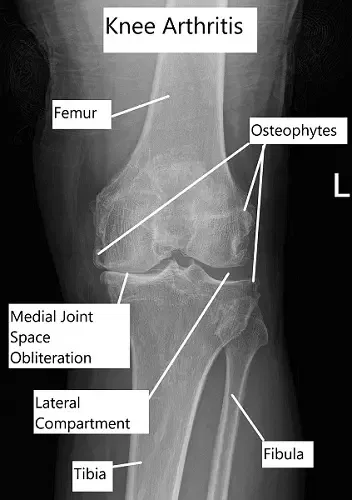

- Imagenología: La radiografía suele ser la primera investigación realizada para comprobar el espacio articular y el engrosamiento de los huesos. Para una evaluación detallada, se puede realizar un TAC, pero normalmente la resonancia magnética es la investigación más útil. Detalla todas las estructuras dentro de la articulación.

- Etapa intermedia: Los nuevos vasos sanguíneos invaden el hueso subyacente al cartílago articular, llamado hueso subcondral, y aumentan su tamaño. La degradación del cartílago continúa hasta que se rompe y se disuelve en la articulación o pasa a ser «cuerpos sueltos». El engrosamiento óseo es especialmente más prominente hacia los lados de la articulación, formando espolones óseos.

- Etapa avanzada: Se pierde cartílago articular con un hueso subyacente engrosado e hinchado. Se desarrollan quistes o cavidades en el hueso y el tejido sinovial aumenta de tamaño debido a la hinchazón. Existe una mayor presión en las articulaciones.